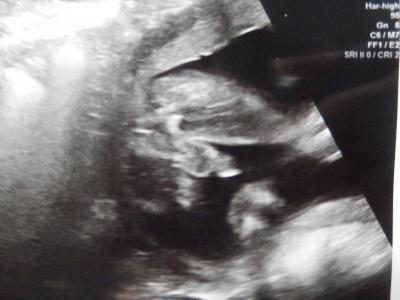

jetzt kann ich endlich loslegen mit dem Nähen Hab sogar ein Foto gekriegt, damit ich nach der Geburt reklamieren kann, falls es doch kein Junge wird! Also scheint es sehr sicher zu sein, dass wir eine Jungsgang werden. Hab ja schon 2 und noch ein Kind gibt es in diesem Leben nicht für mich. Ich finds toll, auch wenn ich gerne mal Zöpfe geflochten hätte... hier noch der Beweis

Bild zu Outing! - Forum für August - Mamis

Hallo, na da fällt nix mehr ab das ist eindeutig. Übrigens kannst du es ja trotzdem mit dem haare flechten vielleicht steht er ja auf lange haare. mein sohn meinte das ich nach dem kleinen jetzt noch zwei jungs und ein Mädchen kriegen soll dann hat er genug geschwister. na mal sehen ob er es nach der Geburt auch noch so sieht. Lg nita

Herzlichen Glückwunsch zum jungen also das ist mehr wie eindeutig!!!!!! Das kannst du nicht mehr reklamieren

Herzlichen Glückwunsch.ist das der Hoden?das sieht so riesig aus...lach